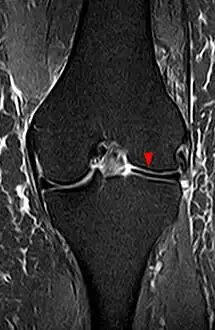

The transverse diameter of a normal meniscus is approximately 10 to 11 mm; therefore a normal meniscus body will be visible on only 2 slices of a MR with 4-5-mm sagittal slices. A discoid meniscus should be considered if more than two contiguous body segments are present. However, this method may lead to a false negative when evaluating people with the Wrisberg variant of discoid meniscus since it maintains a narrow crescent shape. Coronal and radial images of the meniscus are useful to demonstrate the extension of the aberrant meniscus into the joint as seen here. On coronal images, it is diagnosed when the horizontal measurement between the free margin and the periphery of the body is more than 1.4 cm.[1] Rarely, X-ray may show lateral joint space widening, squaring of the lateral condyle, cupping of the lateral tibial plateau and hypoplasia of the lateral tibial spine that suggest discoid meniscus.

Discoid meniscus on coronal proton-density weighted MRI